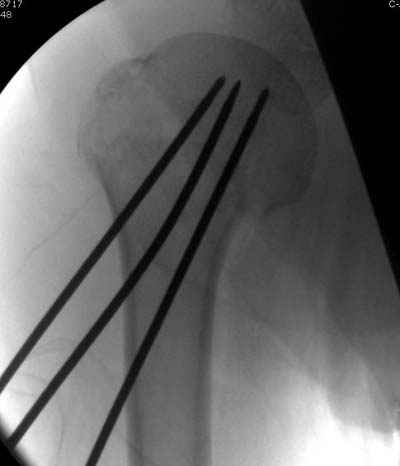

Здравствуй Женя. Во первых спицы, вводимые в головку плеча ретроградно, никогда не имели V-образную форму, если говорить о методике моей операции ЦИТО. Чтобы легче было запомнить Y-образную форму, вспомни крепление новогодних елочных шаров - очень демонстративно. Кроме того если ты внимательно посмотришь, то увидишь, что вся конструкция имеет некоторую кривизну по плокскости, величину, которой ты можешь задать сам. Сначала мы проводим проксимальный пучок, а в момент пересечения линии перелома мы

ротируем спицу таким образом, чтобы дистальный изгиб прямо противодействовал смещающим силам - поврот за ушко под контролем ЭОПа. Дистальный пучок стараемся провести так, чтобы его бранши расклинились и прошли по обе стороны предыдущего пучка, что создает дополнительное напряжение на

протяжении контакта. Для оценки правильности проведения спиц очень важно, чтобы ЭОП стоял строго перпендикулярно плоскости сустава, в противном случае - в рентгене есть эффект отбрасывания тени - прохождение косого луча дает удлиненное изображение спиыц и создается впечатление, что спица стоит уже в субхондральном слое. На первых операциях у нас было довольно частое несовпадение длины контрольной спицы и мы провизорно добавляли от 0,5 до 1,0 см уже на фиксирующем пучке. Входные отверстия лучше располагать по наружной и передней поверхности плеча на расстоянии не менее 2-х диаметров головки.

Такой выбор входных отверстий обусловлен прямой возможностью попадания в малый и большой бугорки за счет изгиба спиц по длине и отражения из от внутреннего кортикала проксимальнее точки введения. Поскольку анатомически бугорки не составляют артикулирующую поверхность, то некоторое выстояние спиц только усилит стабильность. Входное отверстие мы используем 6 мм в диаметре, для эффективного раскрытия петли-пружины. Спицы перед проведением

проверяем на достаточную эластичность и упругоустойчивость, мягкие спицы отбраковываем. В данном примере создалось впечатление, что одна бранша V-спицы скользнула по картикалу снаружи? Все это безболезненно можно переделать, расширив теже отверстия, изогнув спицы, повернув их в разные стороны и добавив еще пучки Y-ОБРАЗНЫХ, а не V-образных (эти пучки выталкивает, особенно если они прямые - пружина работает в обе стороны).

Что-то, наверно, сделали мы не совсем оптимально, поскольку у Анатолия Федровича и его соратников как-то красивее "раскрываются" спицы в головке плеча - надеюсь, он прокомментирует и подскажет, что надо подправить.